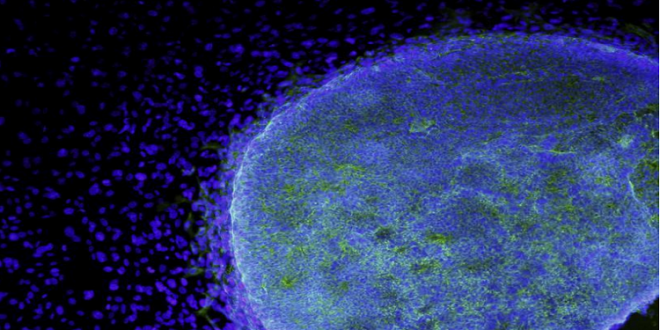

نجح الباحثون في إنشاء غدة التوتة الاصطناعية القادرة على قتل مسببات الأمراض المسؤولة عن نمو الأورام السرطانية.

ويستخدم الجهاز الاصطناعي الخلايا الجذعية في الدم لإنشاء “غدة اصطناعية” قادرة على إنتاج خلايا تائية متخصصة، يمكنها الكشف عن نطاق واسع من الفيروسات، على غرار عمل الخلايا الطبيعية.